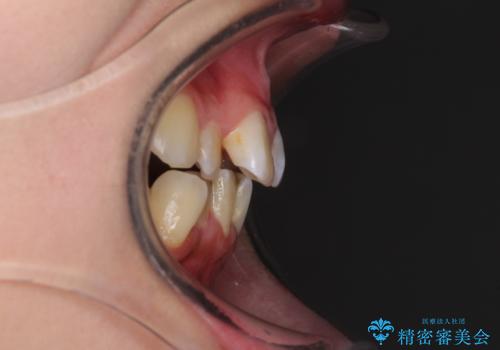

- 上下前歯のデコボコと、それによる磨きづらさを気にして来院された患者様です。

叢生解消のため、上下左右第一小臼歯4本を抜歯し、ワイヤー装置にて矯正治療を行うこととしました。